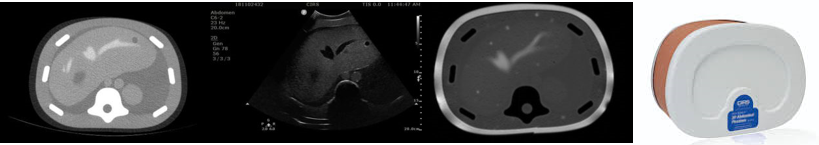

The segmentation (i.e., the voxel labelling) and mesh extraction have a computational cost linear to the number of voxels composing the volumetric image. Table 1 reports the timing of each algorithm step on an 11th generation Intel(R) Core(TM) i7-11700k 8 core. To better integrate the approach with existing clinical workflow, we tested its robustness to subsampling. Indeed, given the computational cost property of the method, even a light subsampling could drastically improve the performance in terms of time required for the segmentation to complete. Fig. 5 shows how skin segmentation remains clean and accurate given an image and its subsampled version. We subsampled a volume image by a factor of two in each direction. The only difference is in the resolution of the surface, which is a direct consequence of the lower resolution of the subsampled original image. To confirm the maintained accuracy of the segmentation at different image resolutions, we computed the distance distribution between the surfaces extracted from a volume image and its subsampled version. In this case, the higher distances correspond to those slices and pixels missing in the subsampled version of the image, and the value of the distance is coherent with the changed dimension of the voxels. The 3D skin segmentation, contrary to AI methods, does not require any training and consequently does not require a large data set or various acquisition of diverse imaging modalities, contributing to the method’s generality. The skin segmentation has been designed to be as general as possible regarding the anatomical area scanned (e.g., head, breast, total body and abdomen) and the acquisition modality (e.g., MR, CT, PET). We tested the quality of the segmentation on different anatomical volume images, such as CTs and MRIs (Fig. 6), obtaining satisfactory results.

The co-registration experimental tests were performed on both the phantom of the abdomen and real subjects. The error on a phantom is related mainly to the camera position, the acquired area’s limited dimension, and its symmetric shape. The accuracy inside the volume with the phantom tests is satisfactory since the error remains within an acceptable range (i.e., under 1 cm), and the physician can quickly correct the smaller error through a fast tuning performed manually to produce a more accurate result (if needed). To verify the robustness of the co-registration, the skin surface was captured by placing the 3D camera at different distances from the skin (Fig. 7). The co-registration remains stable against the acquisition distance. At very high distances, the noise acquired by the camera increases, confirming the algorithm’s robustness to the noise and symmetries, which are typical of the phantom but unlikely in real subjects. Fig. 8 shows the co-registration on CT/MRI images of real subjects. We tested how much tilting the 3D camera at various angles during the acquisition would affect the co-registration. From the camera’s specifications, the ideal acquisition angle is 45 degrees to avoid distortions in the acquired 3D surface. Fig. 9 shows the co-registration when the camera is tilted by 45 degrees, which has the best co-registration due to the higher quality of the acquired surface, and when the camera view is perpendicular to the patient’s surface. The additional noise with a view angle of 45 degrees does not interfere with the co-registration, which includes the automatic identification of regions of interest both on the segmented surface and the 3D surface acquired by the camera. This region of interest identifies correspondent regions on the two surfaces and notably reduces the inclusion of noise from the 3D camera. To verify the influence of the selection of corresponding virtual landmarks on the co-registration, we select slightly displaced markers along the , the axes and a diagonal ( and displacement) directions and measure the changes of the angles between the corresponding co-registration matrices. Considering increasing displacements on the landmark selection, significant differences in the rotation angles were not found (Fig. 10). The robustness of the co-registration to a misplacement of the reference virtual landmarks confirms that the algorithm will not be user-dependent, i.e., the users can apply different approaches to select the landmark.

The accuracy of the US/MR image fusion has been tested on an abdominal phantom CIRS Model 057. The phantom tests have been conducted on the CT (Fig. 11) and MR (Fig. 12) images. The skin surface has been acquired by segmenting the CT acquisition of the phantom. In contrast, the 3D surface obtained by the camera was captured by moving the camera around the phantom to simulate a better possible clinical configuration, where the EM transmitter and camera are placed around the patient bed. The accuracy result is better in the 0 degrees and 180 degrees with respect to the lateral one (90-180). In the worst-case scenario, the accuracy error varies from 4.3mm to 13 mm.